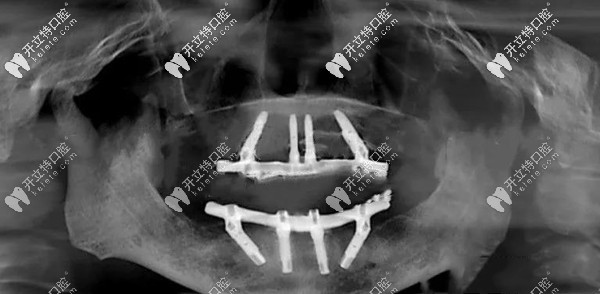

上面是我做完全口種植牙后3個(gè)月,拍的CT片▲

我做的是ALL-ON-4全口即可負(fù)重種植牙,當(dāng)天戴上臨時(shí)牙冠就不耽誤吃飯了~~恢復(fù)后吃東西和原來的真牙差不多,不磨嘴、也沒啥異物感,啃排骨、吃蘋果等都是常有的事!

考慮到我的牙槽骨萎縮情況,就選這個(gè)ALL-ON-4全口即刻負(fù)重種植技術(shù)~~手術(shù)整個(gè)過程大概用了2個(gè)多小時(shí),真沒有自己想象的那么疼。